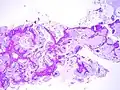

Adénocarcinome pulmonaire in situ mucineux

L'adénocarcinome pulmonaire in situ (ou carcinome bronchioloalvéolaire) est une variété non invasive d'adénocarcinome pulmonaire. Par convention, il doit avoir un diamètre inférieur à 3 cm.